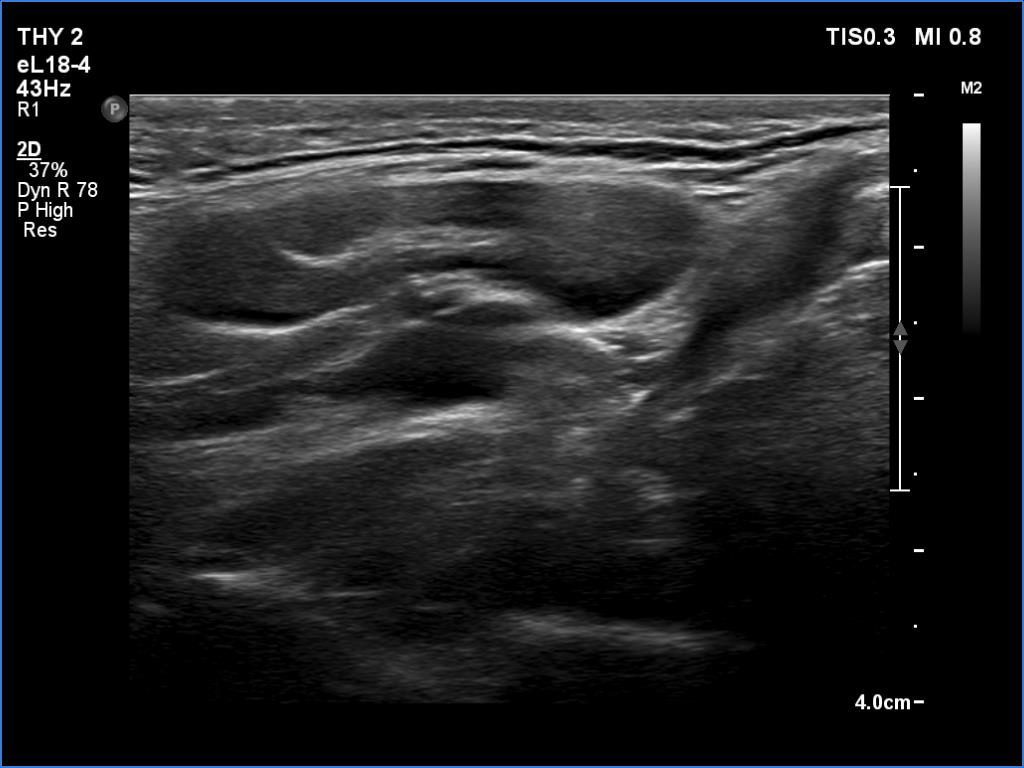

Follow-up examination 8 years later (4th and 5th rows of images):

Ultrasonography revealed hypoechoic discrete lesions in both thyroid lobes. The lesions presented microcalcifications. Corresponding to the palpable mass in the right submandibular region, a reactive-type regular lymph node was found. There was an enlarged lymph node in the left submandibular region. The node had a regular hilum but displayed a heterogeneous pattern.

Comment. Until the final histological examination is completed, I would like to draw attention to two things. One is the heterogeneity of the left lymph node and the other is the size and structure of the lesions in the thyroid beds - these features are suspicious of thyroid cancer.